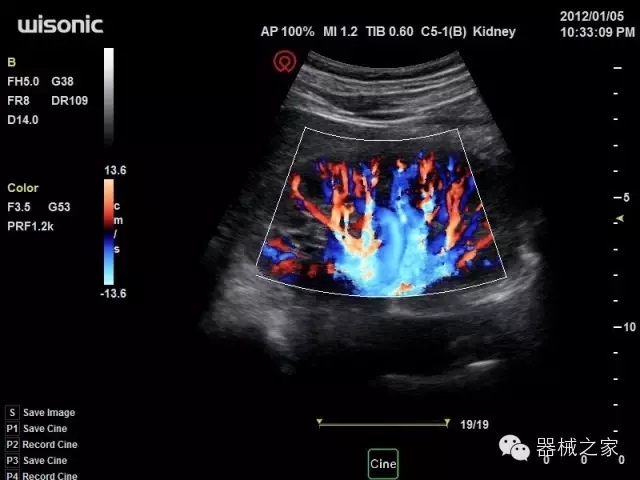

品牌:華聲醫(yī)療(WISONIC)

深圳華聲醫(yī)療技術(shù)有限公司成立于2012年,位于深圳南山西麗湖畔。是一家從事醫(yī)療設(shè)備研發(fā)、制造、營(yíng)銷的新興高新技術(shù)企業(yè),目前提供生命信息支持、數(shù)字便攜彩超、移動(dòng)醫(yī)療服務(wù)三個(gè)方面的業(yè)務(wù)解決方案。公司核心創(chuàng)始人均為醫(yī)療設(shè)備行業(yè)領(lǐng)軍人物,在醫(yī)療行業(yè)服務(wù)時(shí)間平均在10年以上,對(duì)行業(yè)和產(chǎn)品積累了深刻的認(rèn)識(shí)。公司在創(chuàng)立之初就有著長(zhǎng)遠(yuǎn)的戰(zhàn)略目標(biāo)和規(guī)劃,致力于醫(yī)療設(shè)備行業(yè)的細(xì)分市場(chǎng),貼近客戶所需,為大眾的健康提供更多關(guān)愛(ài)。

官方網(wǎng)站:www.wisonic.cn

經(jīng)典產(chǎn)品:四葉草

臨床圖片賞析

產(chǎn)品特點(diǎn)

·全球目前唯一一款配備主機(jī)雙探頭接口,整機(jī)重量(含電池)在5公斤以內(nèi)的便攜式彩超;

·一款互聯(lián)網(wǎng)彩超,只要有手機(jī)信號(hào)的地方就可以非常方便地實(shí)現(xiàn)遠(yuǎn)程會(huì)診和病案調(diào)取;

·鎂鋁合金外殼,堅(jiān)固可靠耐用;

·獨(dú)有的HoloTM PW 實(shí)時(shí)3取樣門(mén)PW成像技術(shù),精確進(jìn)行血管診斷;

·一鍵優(yōu)化B、Color、PW,Auto Doppler自動(dòng)識(shí)別血管位置、偏轉(zhuǎn)角度等,提高工作效率;

·30°超廣角精細(xì)偏轉(zhuǎn)成像技術(shù),更優(yōu)異的頻譜圖像;

·W+智能搜索引擎,快速尋找圖像;

·SSD、USB3.0保障開(kāi)機(jī)快,導(dǎo)出圖像更快,減少等待時(shí)間;

·WIFI、網(wǎng)口、3G,多重聯(lián)網(wǎng)方式,全天候保障云端備份,不再擔(dān)心圖像丟失;

CFDA注冊(cè)證編號(hào)

·粵械注準(zhǔn)201522231208